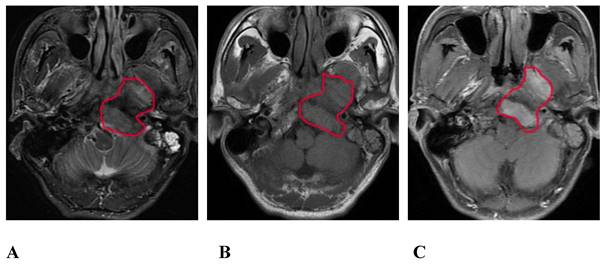

Images of MRI routine sequence

On the routine MRI sequence, bone SBI manifests as bone marrow signal changes or the osteolytic destruction of bone with a low signal on T1WI, a high signal on STIR, and uneven and obvious enhancement on the enhanced scan (Figure 1); meanwhile, muscle SBI manifests as changes in the shape and signal of the muscle such that the signal of the involved muscle is increased on the STIR sequence, and the corresponding area on the enhanced scan shows patchy and uneven enhancement.

Figure 1

A 57-year-old male with SBI in NPC. A, B, and C show the conventional MRI sequence transverse axial STIR, T1WI, and T1WI-enhanced scan sequences, respectively. The red circle shows the clivus, the left processus pterygoidei, and the parapharyngeal muscle involvement. STIR is slightly hyperintense, T1WI is isointense, and the enhanced scan is significantly enhanced. SBI, skull-base invasion; NPC, nasopharyngeal carcinoma; STIR, short-tau inversion recovery; T1WI, T1-weighted imaging.